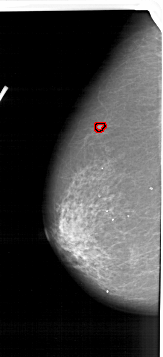

FILE: A_1165_1.LEFT_CC.OVERLAY

TOTAL_ABNORMALITIES 1

ABNORMALITY 1

LESION_TYPE MASS SHAPE OVAL MARGINS ILL_DEFINED

ASSESSMENT 4

SUBTLETY 2

PATHOLOGY MALIGNANT

TOTAL_OUTLINES 1

BOUNDARY